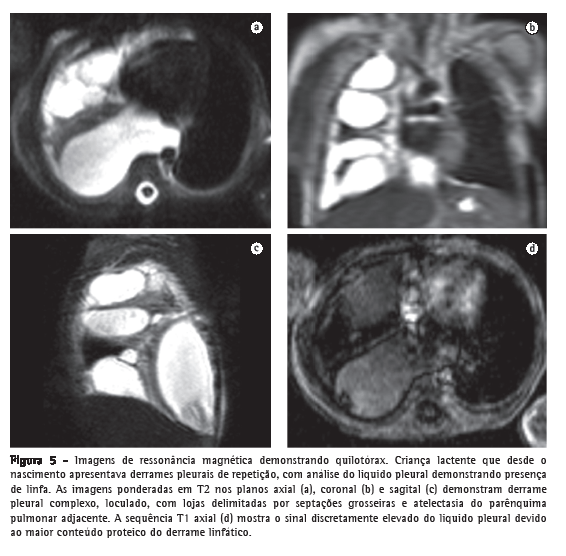

A RM é superior à radiografia e à US na detecção e na caracterização dos derrames pleurais, os quais normalmente aparecem com alto sinal T2 e baixo sinal T1, variando de acordo com o conteúdo de água e proteínas. Em comparação com a TC, a RM é também superior, principalmente na caracterização dos derrames complexos, melhor demonstrando as septações em derrames loculados, assim como na identificação de exsudatos e hemorragias, que demonstram aumento do sinal T1, e de sangramentos antigos, com áreas periféricas de hipossinal por deposição de hemossiderina (Figura 5).(38)